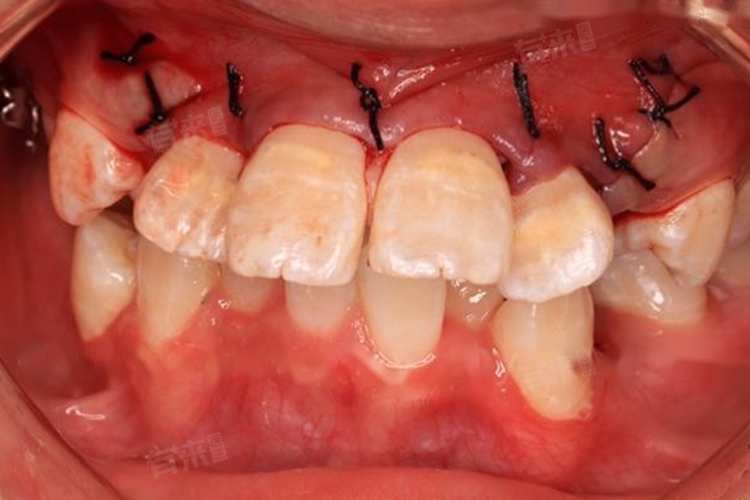

4、外科助萌术:若虎牙埋伏较深,单纯依靠矫正装置难以使其萌出,可能需采用外科助萌术。医生在局部麻醉下,切开牙龈,暴露虎牙牙冠,粘结牵引附件,再通过正畸装置进行牵引,使虎牙逐渐萌出至正常位置。术后需注意伤口护理,预防感染,同时按医嘱配合正畸治疗。